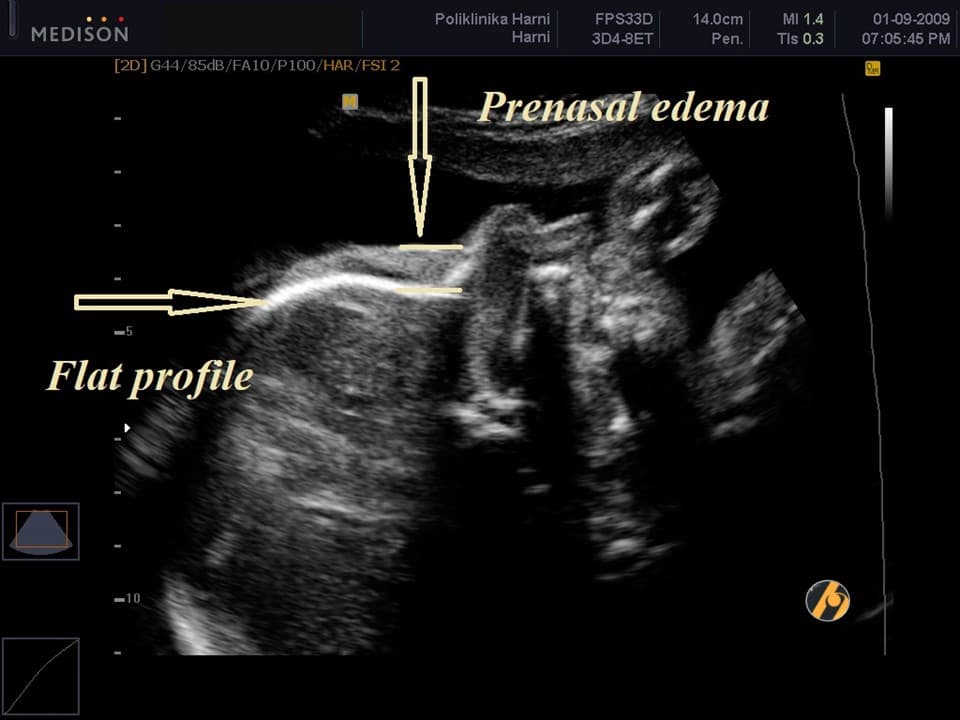

- Specifično okruglo lice s ravnim profilom i malen / hipoplastičan nos uslijed nedostatka ili nerazvijenosti nosne kosti i prenazalni edem,

Ako postoji ultrazvučni biljeg kromosomopatija, procijenjeni rizik se može dobiti množenjem a priori rizika (na temelju rezultata probira) s omjerom vjerojatnosti specifične strukturne anomalije ili markera. Omjer vjerojatnosti za trisomiju 21 je oko 1 (a priori rizik se ne povećava u slučaju ciste koroidnih pleksusa, ehogenog endokardijalnog fokusa, blage hidronefroze i skraćenog femura) i oko 10 (postoji deseterostruko povećanje a priori rizika za nuhalni nabor, prenazalni edem i hipoplastičnu nosnu kost).